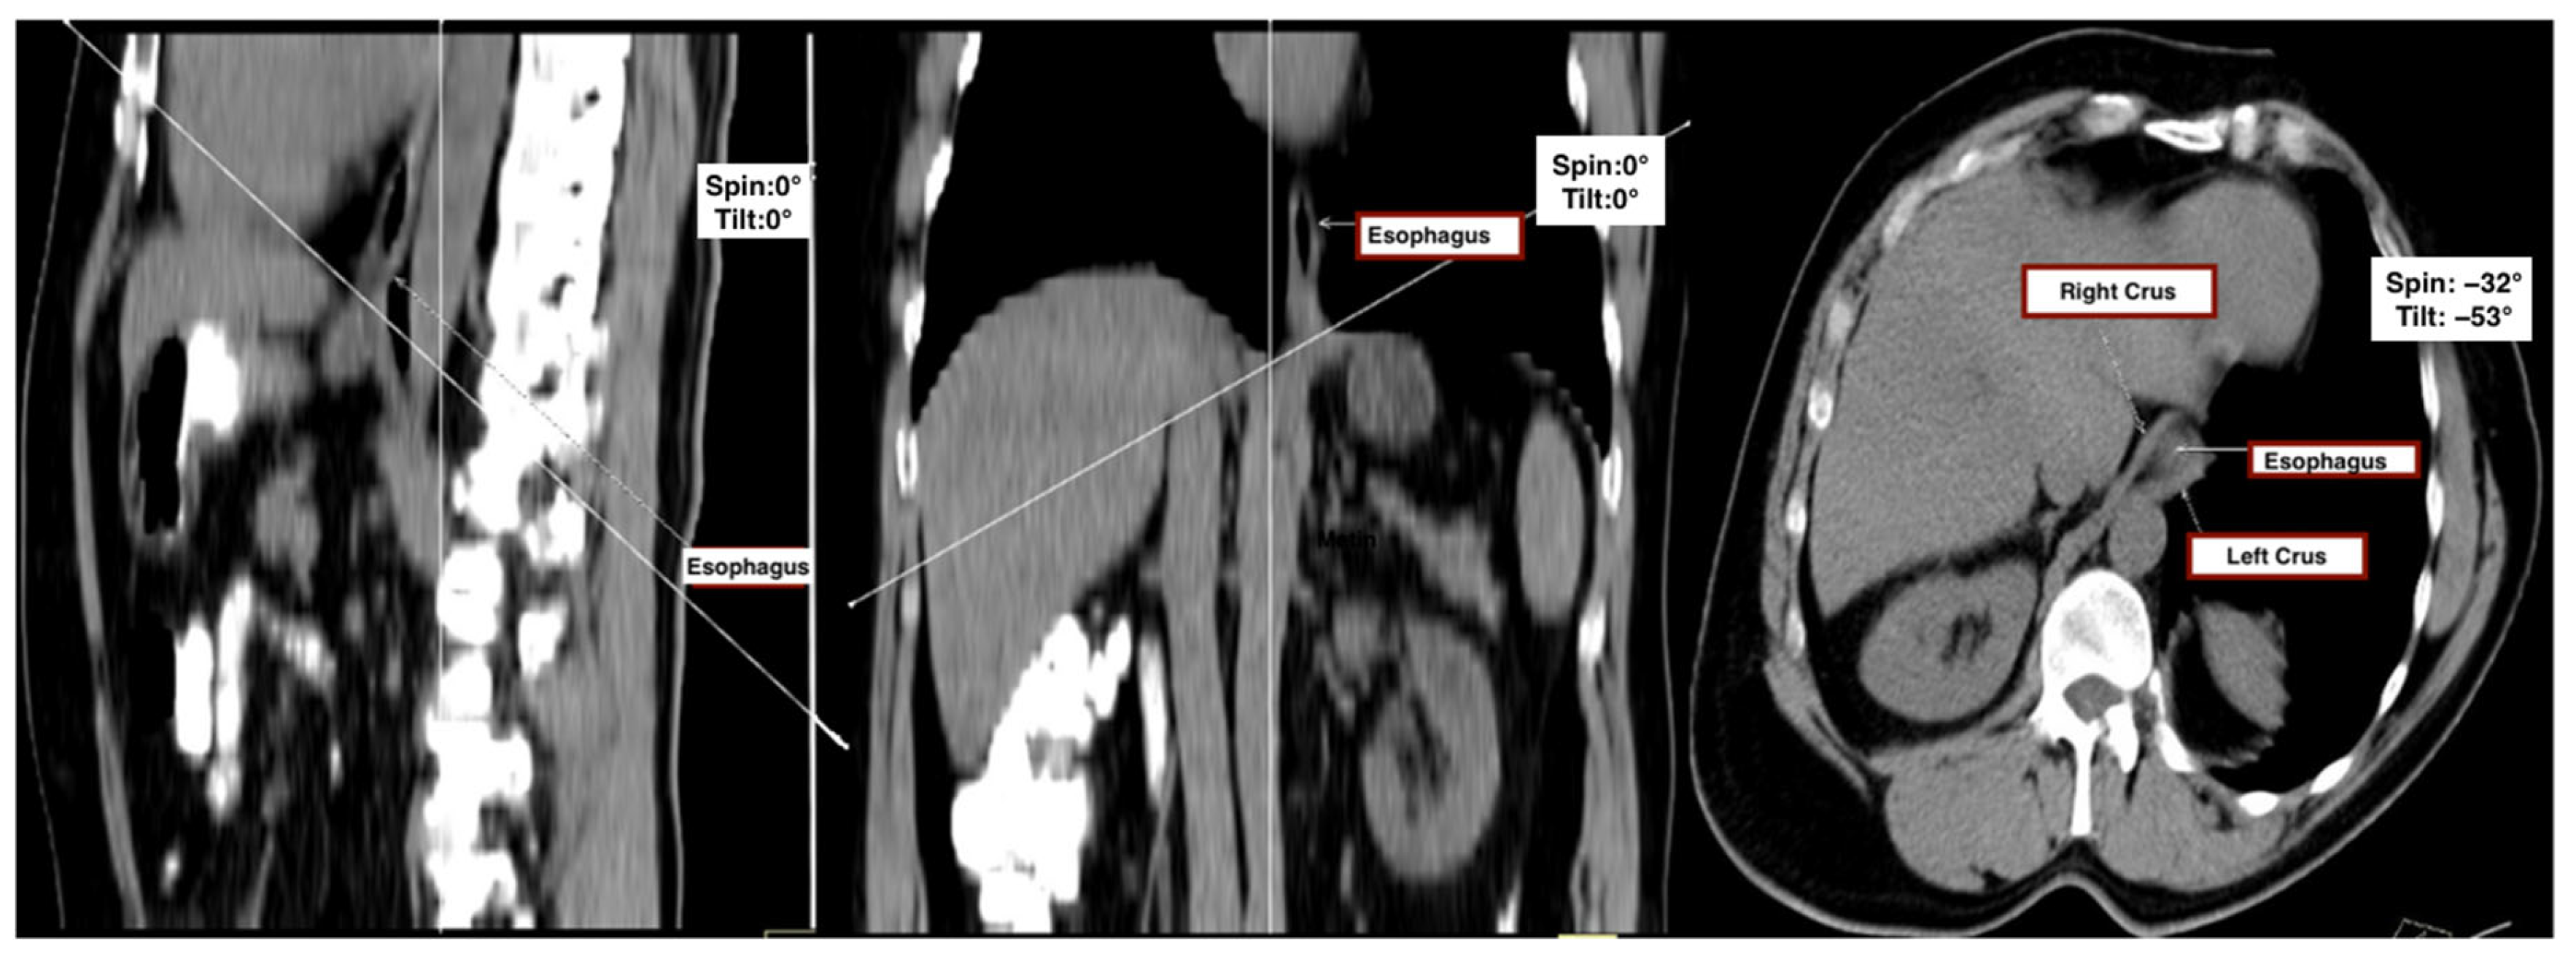

First, sagittal and coronal thoracic planes were used as anatomical references to define a doubly oblique axial plane. The image was realigned to bisect the midline of the vertebral bodies in the sagittal view and to run parallel to the anterior vertebral surfaces in the coronal view. The final oblique axial plane was then defined as perpendicular to the sagittal axis and aligned with the diaphragmatic crura, providing the optimal cross-sectional view of the esophageal hiatus.

This plane, which corresponded closely to intraoperative anatomical appearance and enabled complete visualization of hiatal components, was accepted as the reference plane for all measurements. To assess consistency across patients, the tilt angle (sagittal deviation) and spin angle (coronal deviation) were recorded for each subject (Figure 1).

Figure 1. Multiplanar CT evaluation of the esophageal hiatus. Standardized sagittal (left), coronal (middle), and oblique axial (right) MDCT reconstructions used for anatomical localization and morphometric analysis of the esophageal hiatus. The esophagus and diaphragmatic crura (right and left) are labeled. The oblique axial plane was obtained by aligning with the diaphragmatic crura and orthogonal to the sagittal axis to best visualize the hiatal components for surface area measurement.